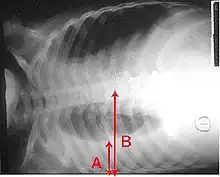

X-ray presentations of pneumonia may be classified as lobar pneumonia, bronchopneumonia, lobular pneumonia, and interstitial pneumonia.[73] Bacterial, community-acquired pneumonia classically show lung consolidation of one lung segmental lobe, which is known as lobar pneumonia.[41] However, findings may vary, and other patterns are common in other types of pneumonia.[41] Aspiration pneumonia may present with bilateral opacities primarily in the bases of the lungs and on the right side.[41] Radiographs of viral pneumonia may appear normal, appear hyper-inflated, have bilateral patchy areas, or present similar to bacterial pneumonia with lobar consolidation.[41] Radiologic findings may not be present in the early stages of the disease, especially in the presence of dehydration, or may be difficult to interpret in the obese or those with a history of lung disease.[24] Complications such as pleural effusion may also be found on chest radiographs. Laterolateral chest radiographs can increase the diagnostic accuracy of lung consolidation and pleural effusion.[40]